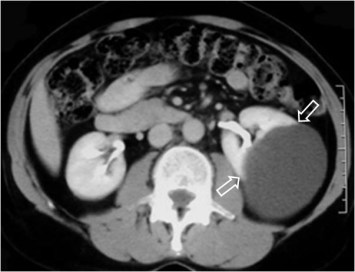

SIGNO DE LA VEJIGA DE PERA

Los traumatismos pélvicos, las adenopatías ilíacas bilaterales, la lipomatosis pélvica y otros procesos, producen una compresión bilateral de la vejiga, que adopta forma de lágrima o de pera.

En la imagen vemos la vejiga de pera en un paciente con traumatismo pélvico. Puede verse la fractura de la rama iliopubiana izquierda y la fractura de ala sacra con luxación sacroilíaca izquierda.

Otro ejemplo de vejiga de pera de origen diferente. Dos cortes contiguos de TC pélvico en un paciente con linfoma muestra el signo debido a la compresión por las masas adenopáticas bilaterales (flechas).